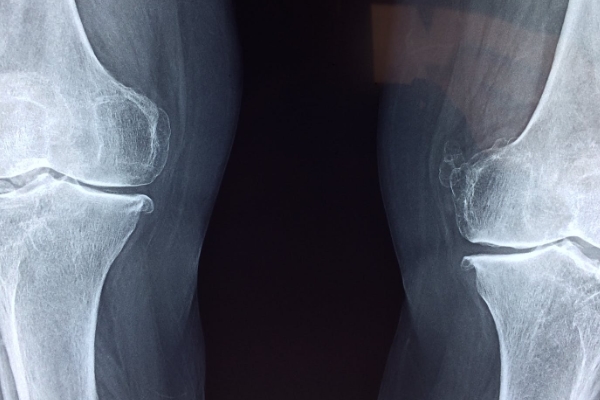

퇴행성 관절염은 관절을 보호하고 있는 연골의 점진적인 손상이나 퇴행성 변화로 인해 관절을 이루는 뼈와 인대 등에 손상이 일어나서 염증과 통증이 생기는 질환으로, 관절의 염증성 질환 중 가장 높은 빈도를 보입니다.

통증은 초기에는 해당 관절을 움직일 때 심해지는 양상을 보이다가 병이 진행되면 움직임 여부에 관계없이 지속적으로 나타나기도 하는데요. 관절 운동 범위의 감소, 종창(부종), 관절 주위의 압통이 나타나며 관절 연골의 소실과 변성에 의해 관절면이 불규칙해지면 관절 운동 시 마찰음이 느껴질 수도 있다고 합니다.